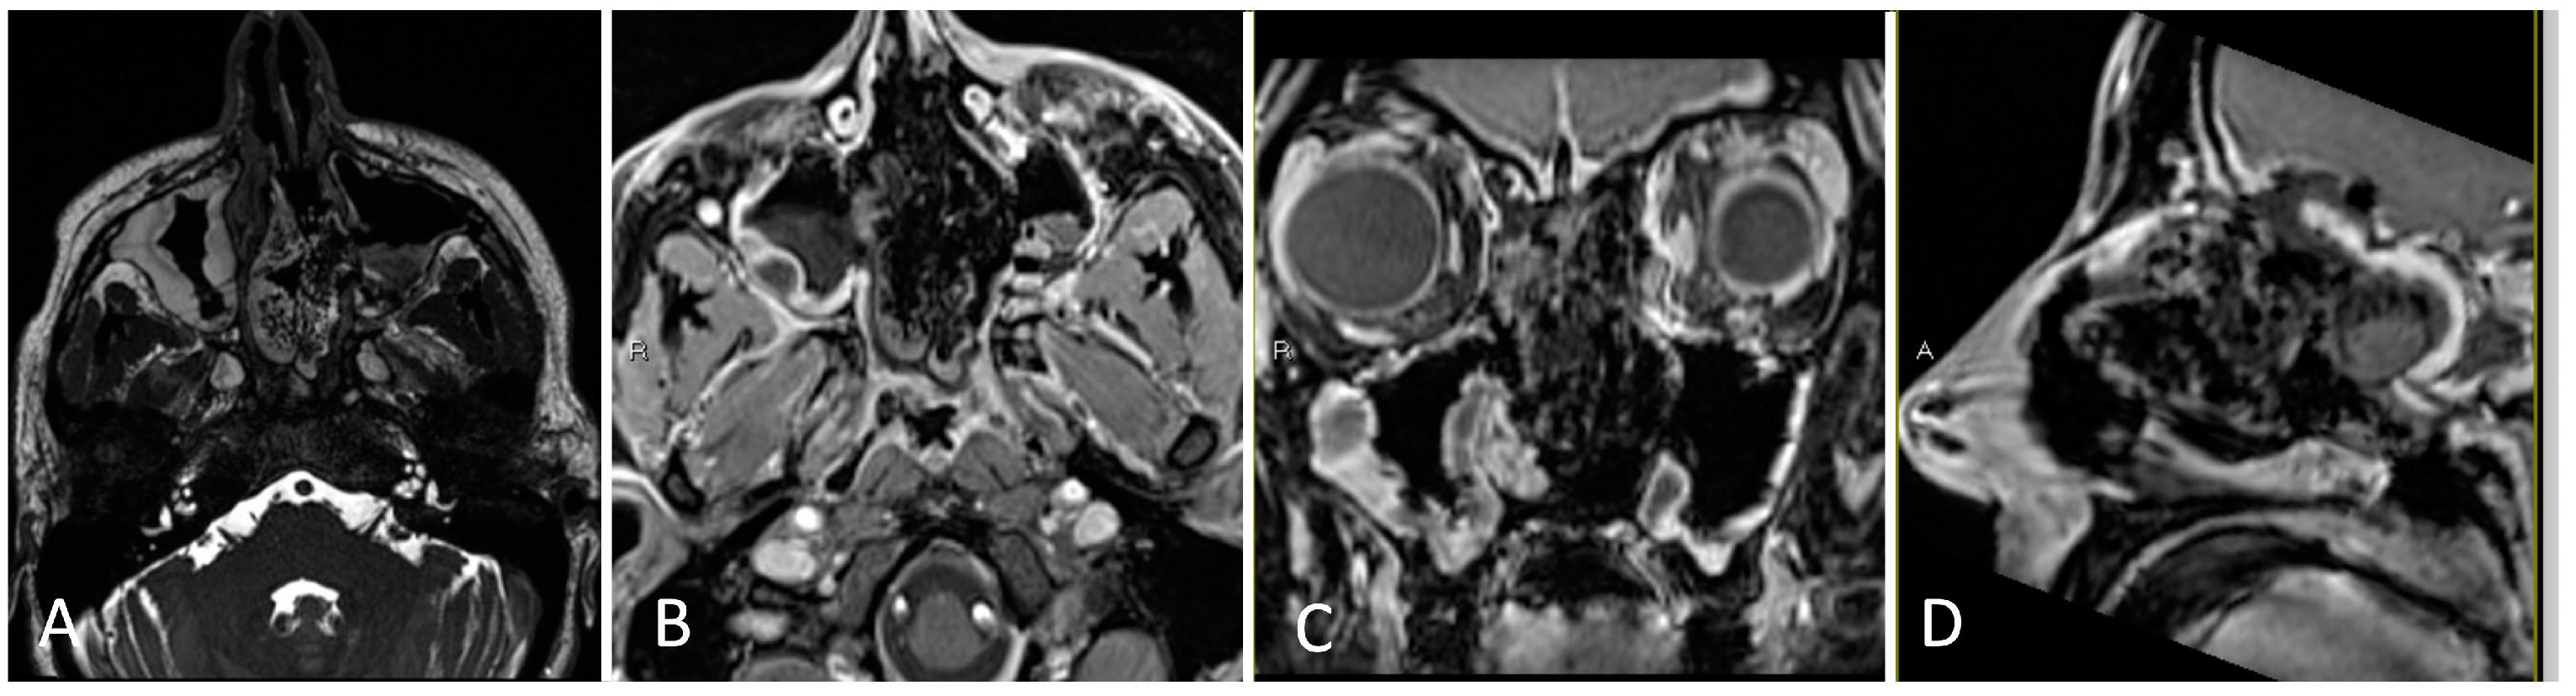

3.1.4. Illustrative Case

3.1.5. Practical Pearls

- Placement of a lumbar drain is advised at the start of surgery, or preoperatively, in cases where a high-flow CSF leak is anticipated, in order to reduce immediate postoperative intracerebral pressure (ICP) and offload excessive pressure on the skull base graft.

- Upfront harvest of a nasal septal flap may be useful for skull base reconstruction in cases of anticipated high flow CSF leak.

- The sphenoid limbus serves as an important landmark for the location of the optic nerves, bridging medial to the optic canal and forming the anterior border of the prechiasmatic sulcus.

- When approaching lesions within the suprasellar region, one should be mindful of the location of the optic apparatus (i.e., pre-fixed/post-fixed chiasm) as well as relevant neurovascular structures in the chiasmatic, lamina terminalis, interpeduncular, and prepontine cisterns.

- Craniopharyngiomas may be fenestrated into a natural CSF space, such as the basal cisterns and third ventricle, to reduce long-term cystic reaccumulation/recurrence.